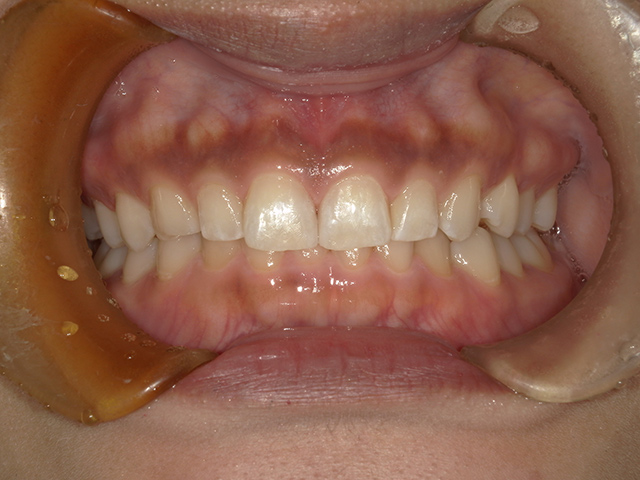

ダイレクトボンディングとは、高品質なレジン(樹脂)を直接歯に盛り付け、形や色を1本1本丁寧にデザインする審美修復治療です。

天然歯のような透明感や質感を再現できるため、近年非常に人気が高まっています。

自然で美しい仕上がり

使用するレジンは、色調・明度・透明感を細かく調整できる審美レジン。

歯科医師が職人のように層を重ねながら形を作り、天然歯と見分けがつかない仕上がりを目指します。

すきっ歯・欠けた歯の修復に最適